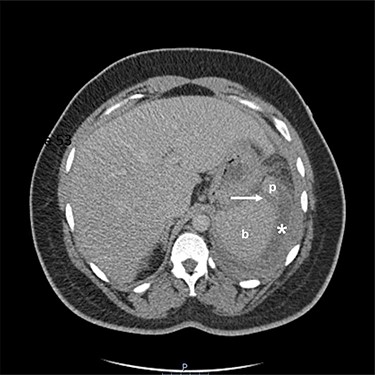

Two-mm axial section from a CT scan showing the perisplenic haematoma (*) and hypodensity (arrow) separating the upper anterior pole of the spleen (p) from the body (b). CT section number 54.